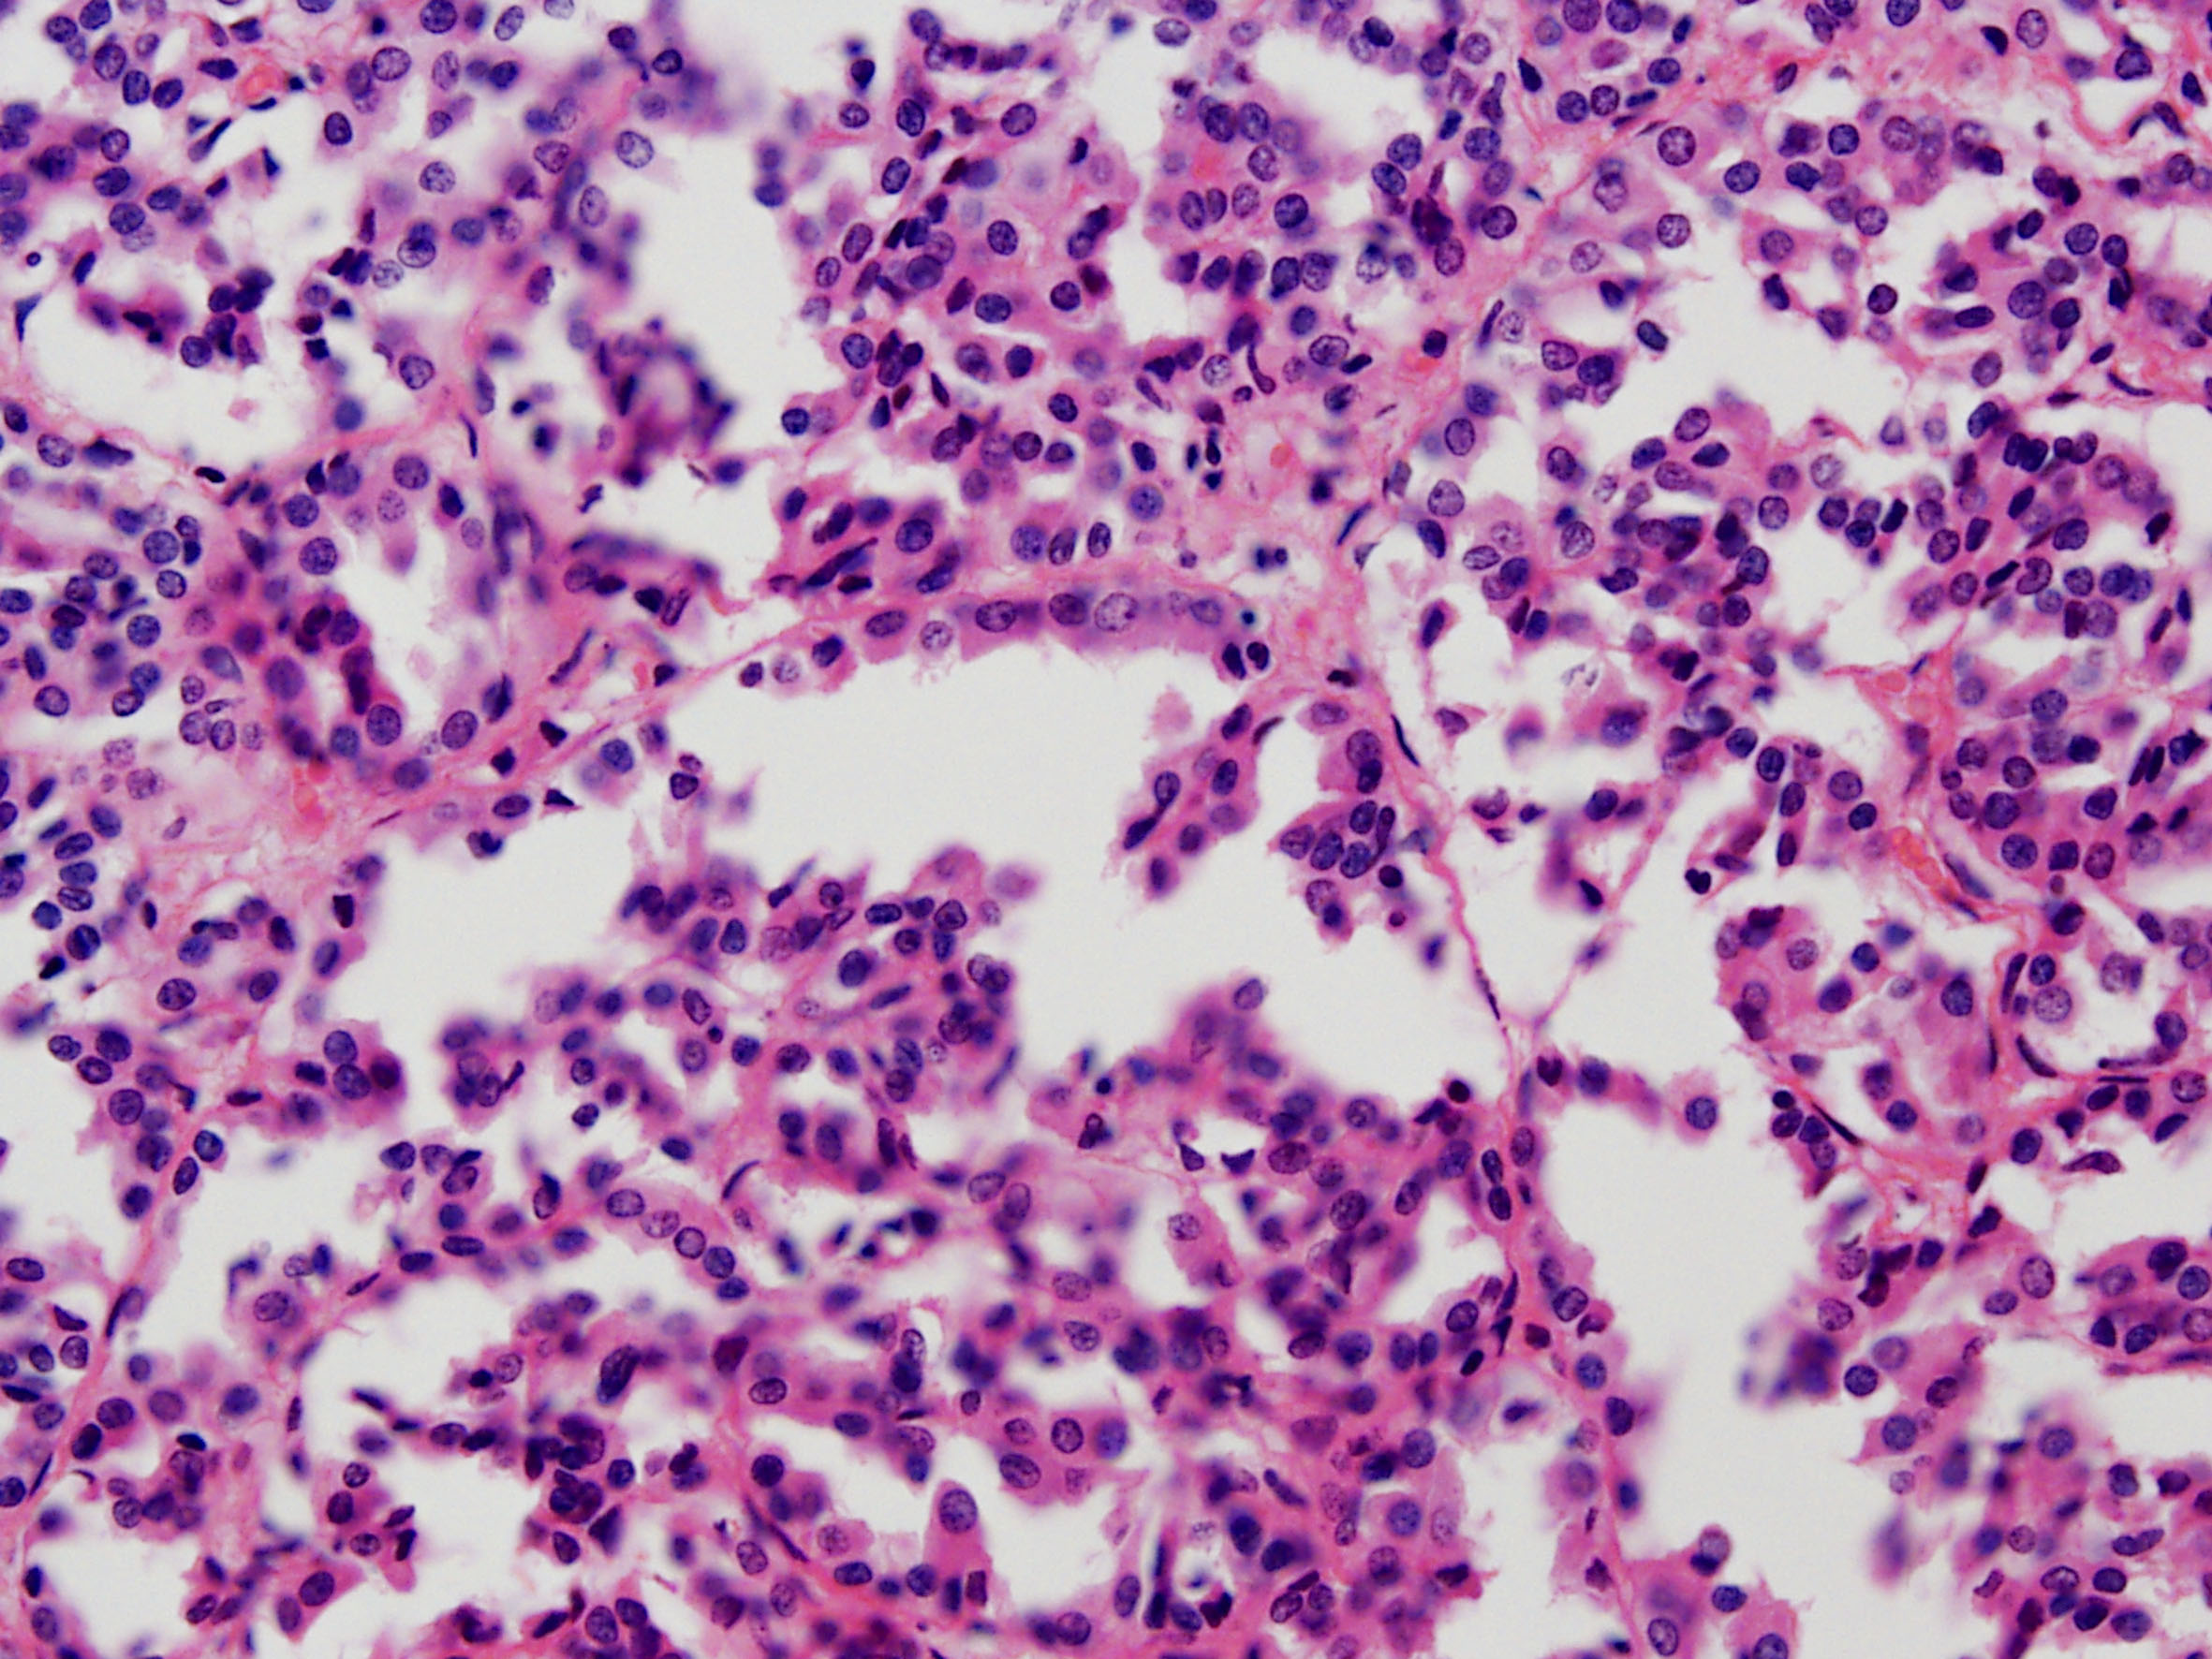

Classification of renal tumors

Case ID: 228